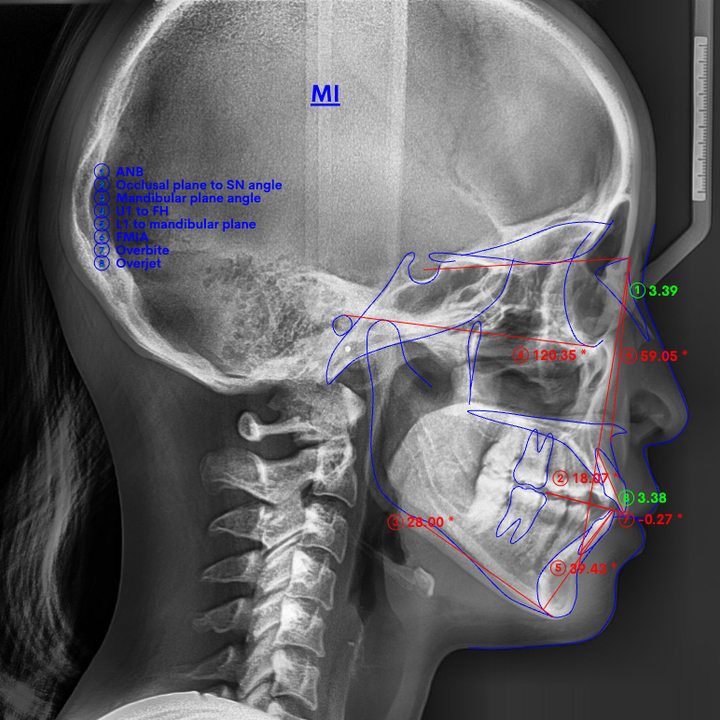

下あごが前にずれて受け口

口呼吸や噛み合わせの問題、あるいは遺伝的な要因で上あごに対して下あごが前にずれると、受け口になってしまいます。

下図のように、下あごが全体的に前に出てしまったため受け口になってしまった、という状態です。

なお、遺伝的に骨格に問題があって下あごがずれている場合は、手術が必要になることもあります。

しかしながら、必要な抜歯を行って前歯を下げるスペースを確保しつつ、奥歯を奥側に動かすことで、受け口の見た目をある程度改善することが可能な場合も少なくありません。